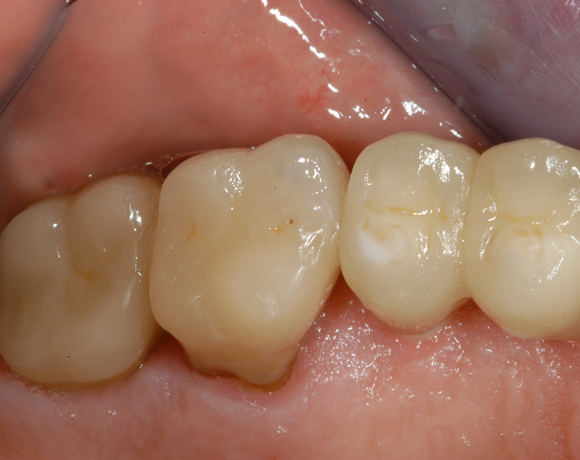

6 Implantate und viele Kronen und Brücken

Mit dem zweiteiligen vollkeramischen Implantat lassen sich auch große Lücken überbrücken.

Im vorliegenden Patientenfall waren die Zähne 11 – 26 mit einer provisorischen Brücke versorgt, der Patient konnte damit aber nicht essen. Auch im Unterkiefer waren die vorhandenen Kronen und Brücken insuffizient. Es wurde eine komplette Neuversorgung für Ober- wie Unterkiefer geplant.